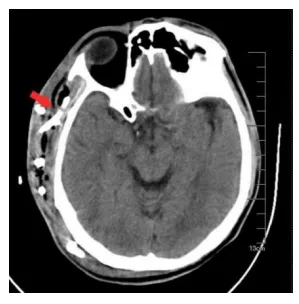

考虑到王先生的情况有可能进一部感染扩散至颅内及纵隔,若病情快速恶化,易诱发脓毒血症,甚至造成多器官功能衰竭等严重并发症,危及生命。因此,介入超声科团队紧急组织院内多学科及科室内部讨论后,认为目前除了抗感染治疗、全身综合治疗以外,应重点考虑如何让脓肿得到充分引流,但颜面部及头颈部为人体暴露部位,且组织间隙脓肿比较散、面积大,使用外科手术创伤大、风险大,尤其对糖尿病患者而言伤口难愈合,因此几乎不考虑外科手术。紧急时刻,郭建琴主任带领团队,反复超声查看病人病灶后,讨论决定实施脓肿穿刺置管引流术。术中,结合CT定位,郭建琴主任团队在超声引导下应用多种穿刺技巧,避开风险部位及血管成功地进行了多管、粗管的充分引流。在介入超声科医生每日的反复冲洗、充分引流下王先生病情得到好转,成功救治28天后王先生完全康复出院,为此他和家属感动不已。